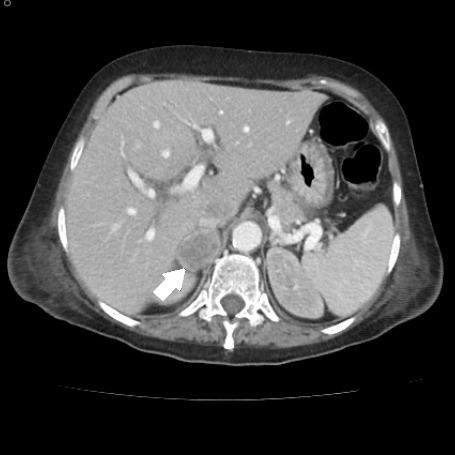

Cholecystocolonic fistula (CCF) is the second most common cholecystoenteric fistula, associated in most cases with stone disease. Symptoms are usually minimal or nonspecific, and preoperative diagnosis is uncommon. Although the incidence of FCC caused by gallbladder cancer comprises 1.7% of cases, it is necessary to suspect it in order to adopt the best therapeutic strategy.

胆囊结肠瘘(CCF)是第二常见的胆囊肠瘘,多数情况下与结石病相关。症状通常轻微或不具特异性,术前诊断并不常见。尽管胆囊癌导致的胆囊结肠瘘发病率占病例的1.7%,但为了采取最佳治疗策略,仍有必要怀疑此病。